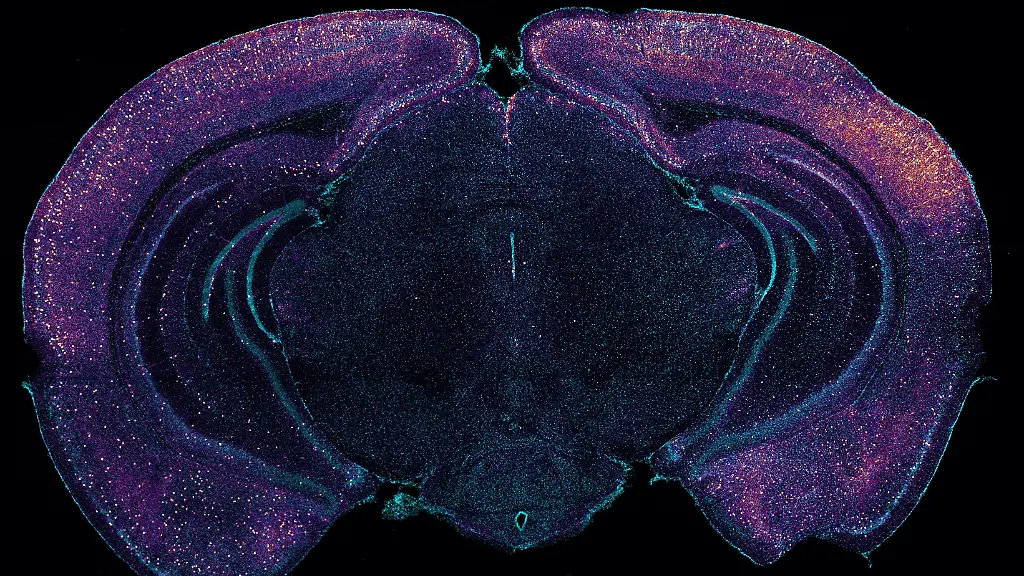

In "Nature" schreibt das Team, bei speziellen genetisch veränderten "Alzheimer-Mäusen" steigere die opto-akustische Stimulierung bei 40 Hz die neuronale Aktivität und senke gleichzeitig die Konzentrationen von Aß im Gehirn. Verantwortlich dafür sei das sogenannte glymphatische System: Der recht neue Begriff kombiniert das lymphatische System - das außerhalb des Gehirns Gewebe reinigt - mit den Gliazellen, die daran maßgeblich im Gehirn beteiligt sein sollen.

Der Studie zufolge sorgt die Stimulierung dafür, dass im Gehirn der Mäuse besonders viel Flüssigkeit durch das Gewebe zirkuliert. Dieses Nervenwasser transportiere das Aß zwischen den Zellen aus dem Gehirn. "Die Zellverbände werden besser durchspült, und der Abfall zwischen den Zellen wird entfernt", erläutert der Neurologe Timmermann, der nicht an der Arbeit beteiligt war. "Das ist faszinierend."